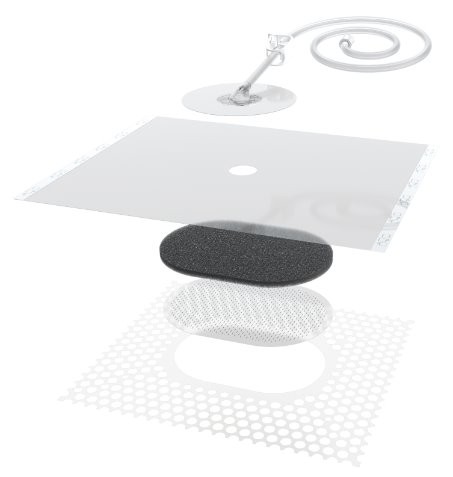

Solventum™ V.A.C.® Peel & Place Dressing

Alles-in-één ontwerp maakt aanbrengen eenvoudig.

1. 3M™ V.A.C.® Granufoam Dressing

Vormt zich naar het wondbed zonder dat er vullers nodig zijn, voor een gelijkmatige negatieve druk en effectieve exsudaatverwijdering.

2. Geperforeerde niet-klevende laag

Hierdoor kan het verband worden aangebracht op de intacte huid rondom de wond, zonder eerst folie te hoeven aanbrengen. De laag is ontworpen om ingroei van weefsel tegen te gaan.

3. 3M™ V.A.C.® Dermatac™ folie

Huidvriendelijke siliconen-acryl kleeftechnologie maakt herpositioneren bij het aanbrengen mogelijk en zorgt voor een goede afdichting op vele anatomische locaties en minimaal ongemak bij het verwijderen.

4. Opening voor Solventum™ SensaT.R.A.C.™ Pad

Voorgeknipt voor eenvoudig en consistent aanbrengen van de SensaT.R.A.C. Pad.

5. Solventum™ SensaT.R.A.C.™ Pad

Helpt de druk in het wondgebied te monitoren en te handhaven.